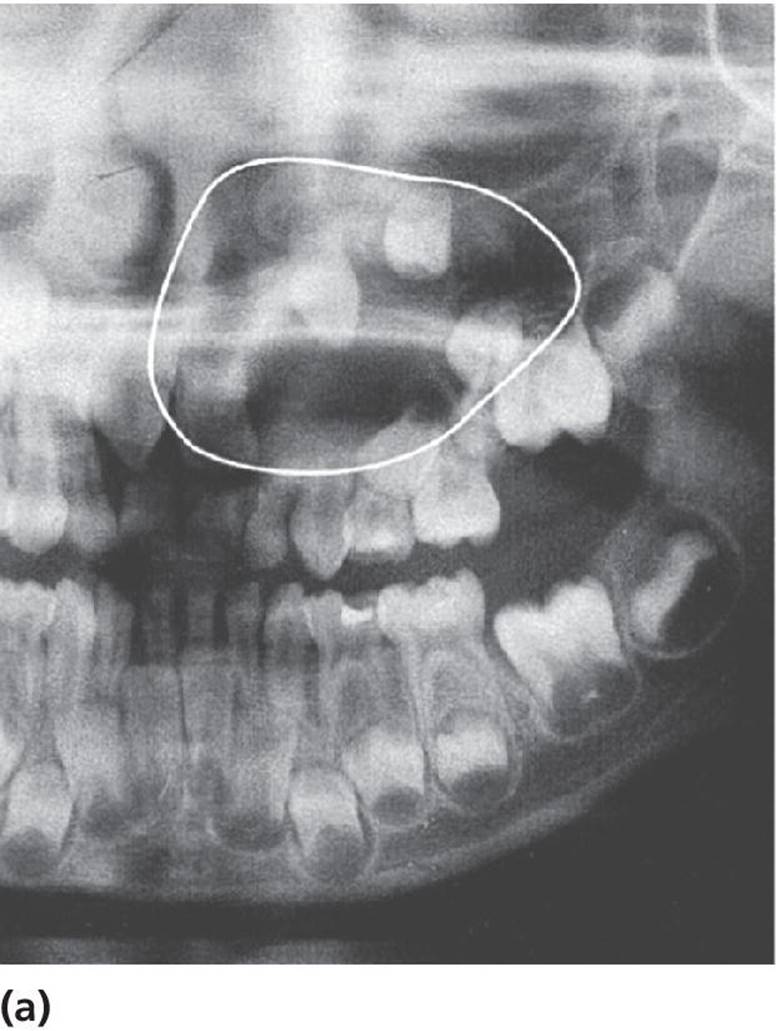

Cysts in the jaws, and especially large follicle cysts emerging from non‐erupted teeth, may displace teeth under development and disturb their eruption (Figure 15.29a–c). In children, it is important not to remove the cysts surgically as a first step procedure since this might damage a number of teeth and tooth germs. Instead, it is recommended in cases with large cysts that the cyst should be shrunk by use of rinsing with saline through an obturator introduced through the cyst wall (Figure 15.29d). In young individuals, the cyst will rapidly decrease and will be substituted by bone and often the dislocated teeth will spontaneously find their normal positions and eruption pathways.

Figure 15.29 (a) Extensive dentigerous (follicular) cyst in left maxilla emerging from a supernumerary tooth and displacing tooth germs and disturbing normal eruption in a 5‐year‐old girl. (b) Radiographic examination after 5 months revealed that the cyst had been reduced considerably and was now available for surgical removal without risk of disturbing the involved teeth. (c) After 4 months and surgical removal of supernumerary teeth and residual cyst tissues. (d) Obturator inserted to facilitate rinsing of the cyst. The obturator was removed after 6 weeks.